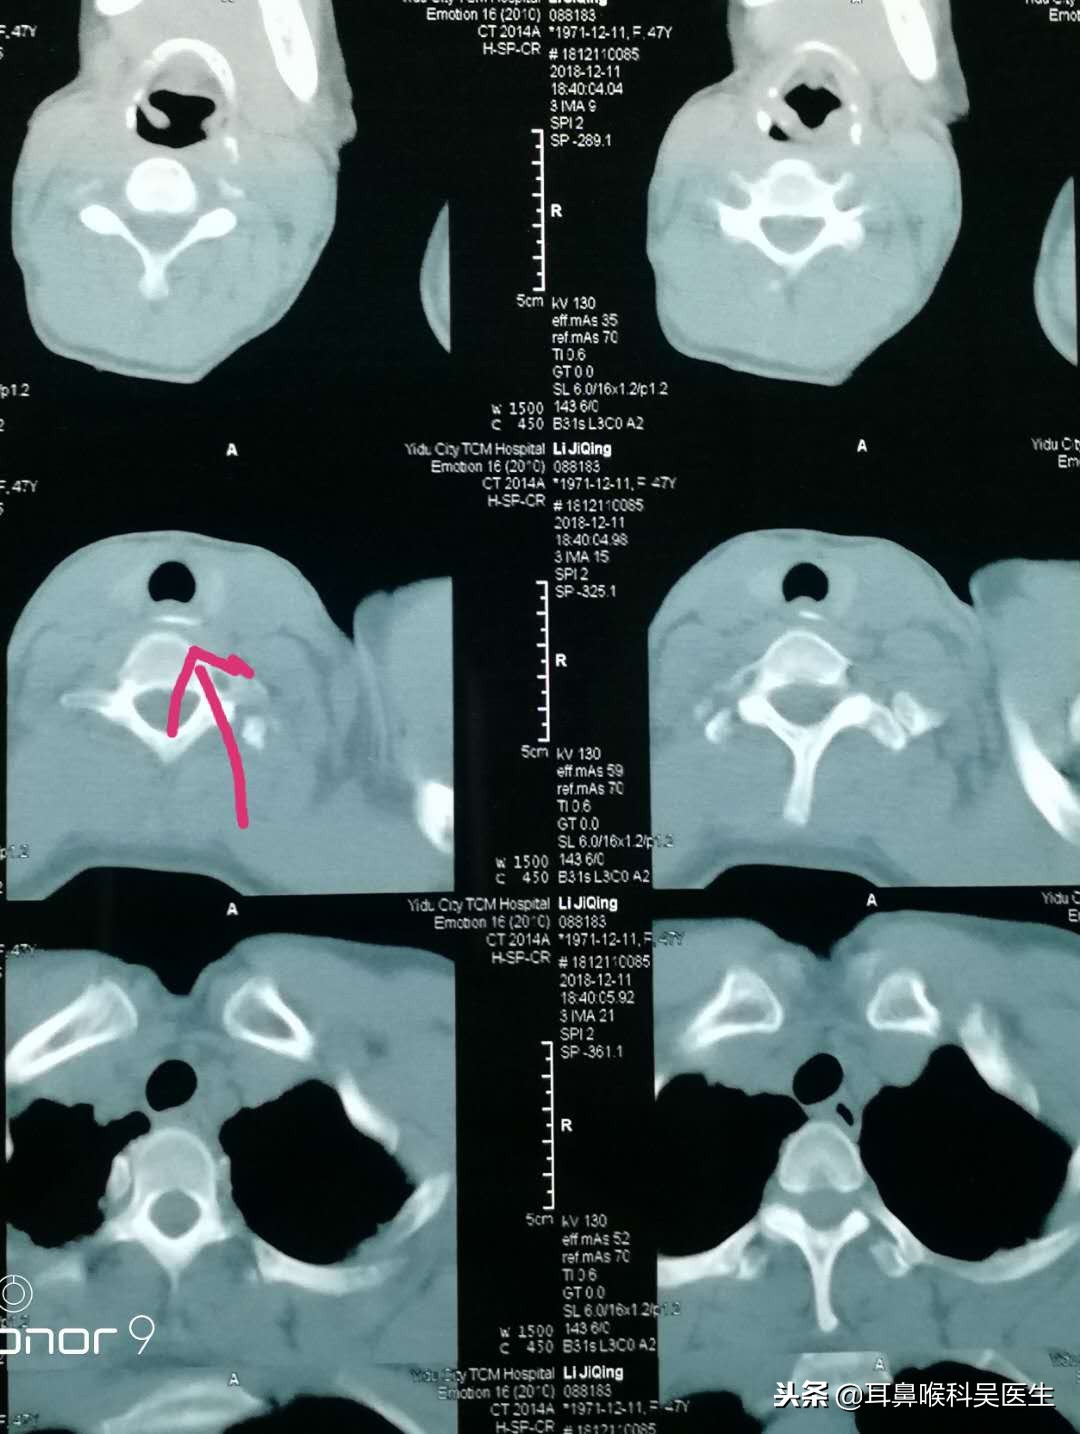

很多人误吞鱼刺等异物后时,不一定能弄清自己的异物到底卡在哪里,这时候,可以选择轻轻咳嗽一下,通过疼痛感来感知异物刺卡住的大概位子,从而判断是自行处理还是及时就医处理。误吞异物的常见被卡部位有左右扁桃体处、舌根部、会厌、食道、喉咙梨状窝。如果异物是在较浅的部位,可通过肉眼观察看到的,可以在现场尝试自行夹出。但如果是卡在比较深的部位如会厌、舌根等位子,则需要通过医院专业器材来取出。这些部位黏膜柔软脆弱,食道相邻还有大血管,错误处理鱼刺等异物,可能会让食道出血,黏膜受伤发炎等。